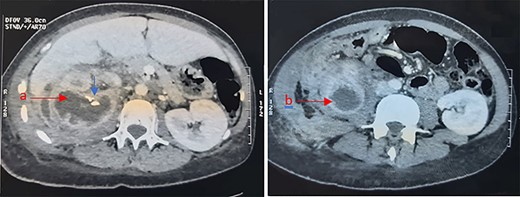

Interstingly, anatomopathological examination of the operative specimens reported the aspect of hydatid renal cyst (Fig. 2a and b).

(a) Renal parenchyma with inflammatory reaction containing hydatid membranes (×10). (b) Eosinophil hydatid membranes and laminated acellular layers (×40).